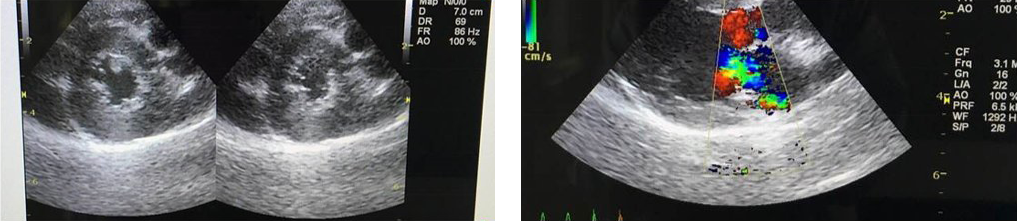

エコー検査は超音波を用いて心臓を視覚的にイメージするものです。

この安全かつ簡便な方法によって、心臓の構造や機能に関する情報を得ることができます。